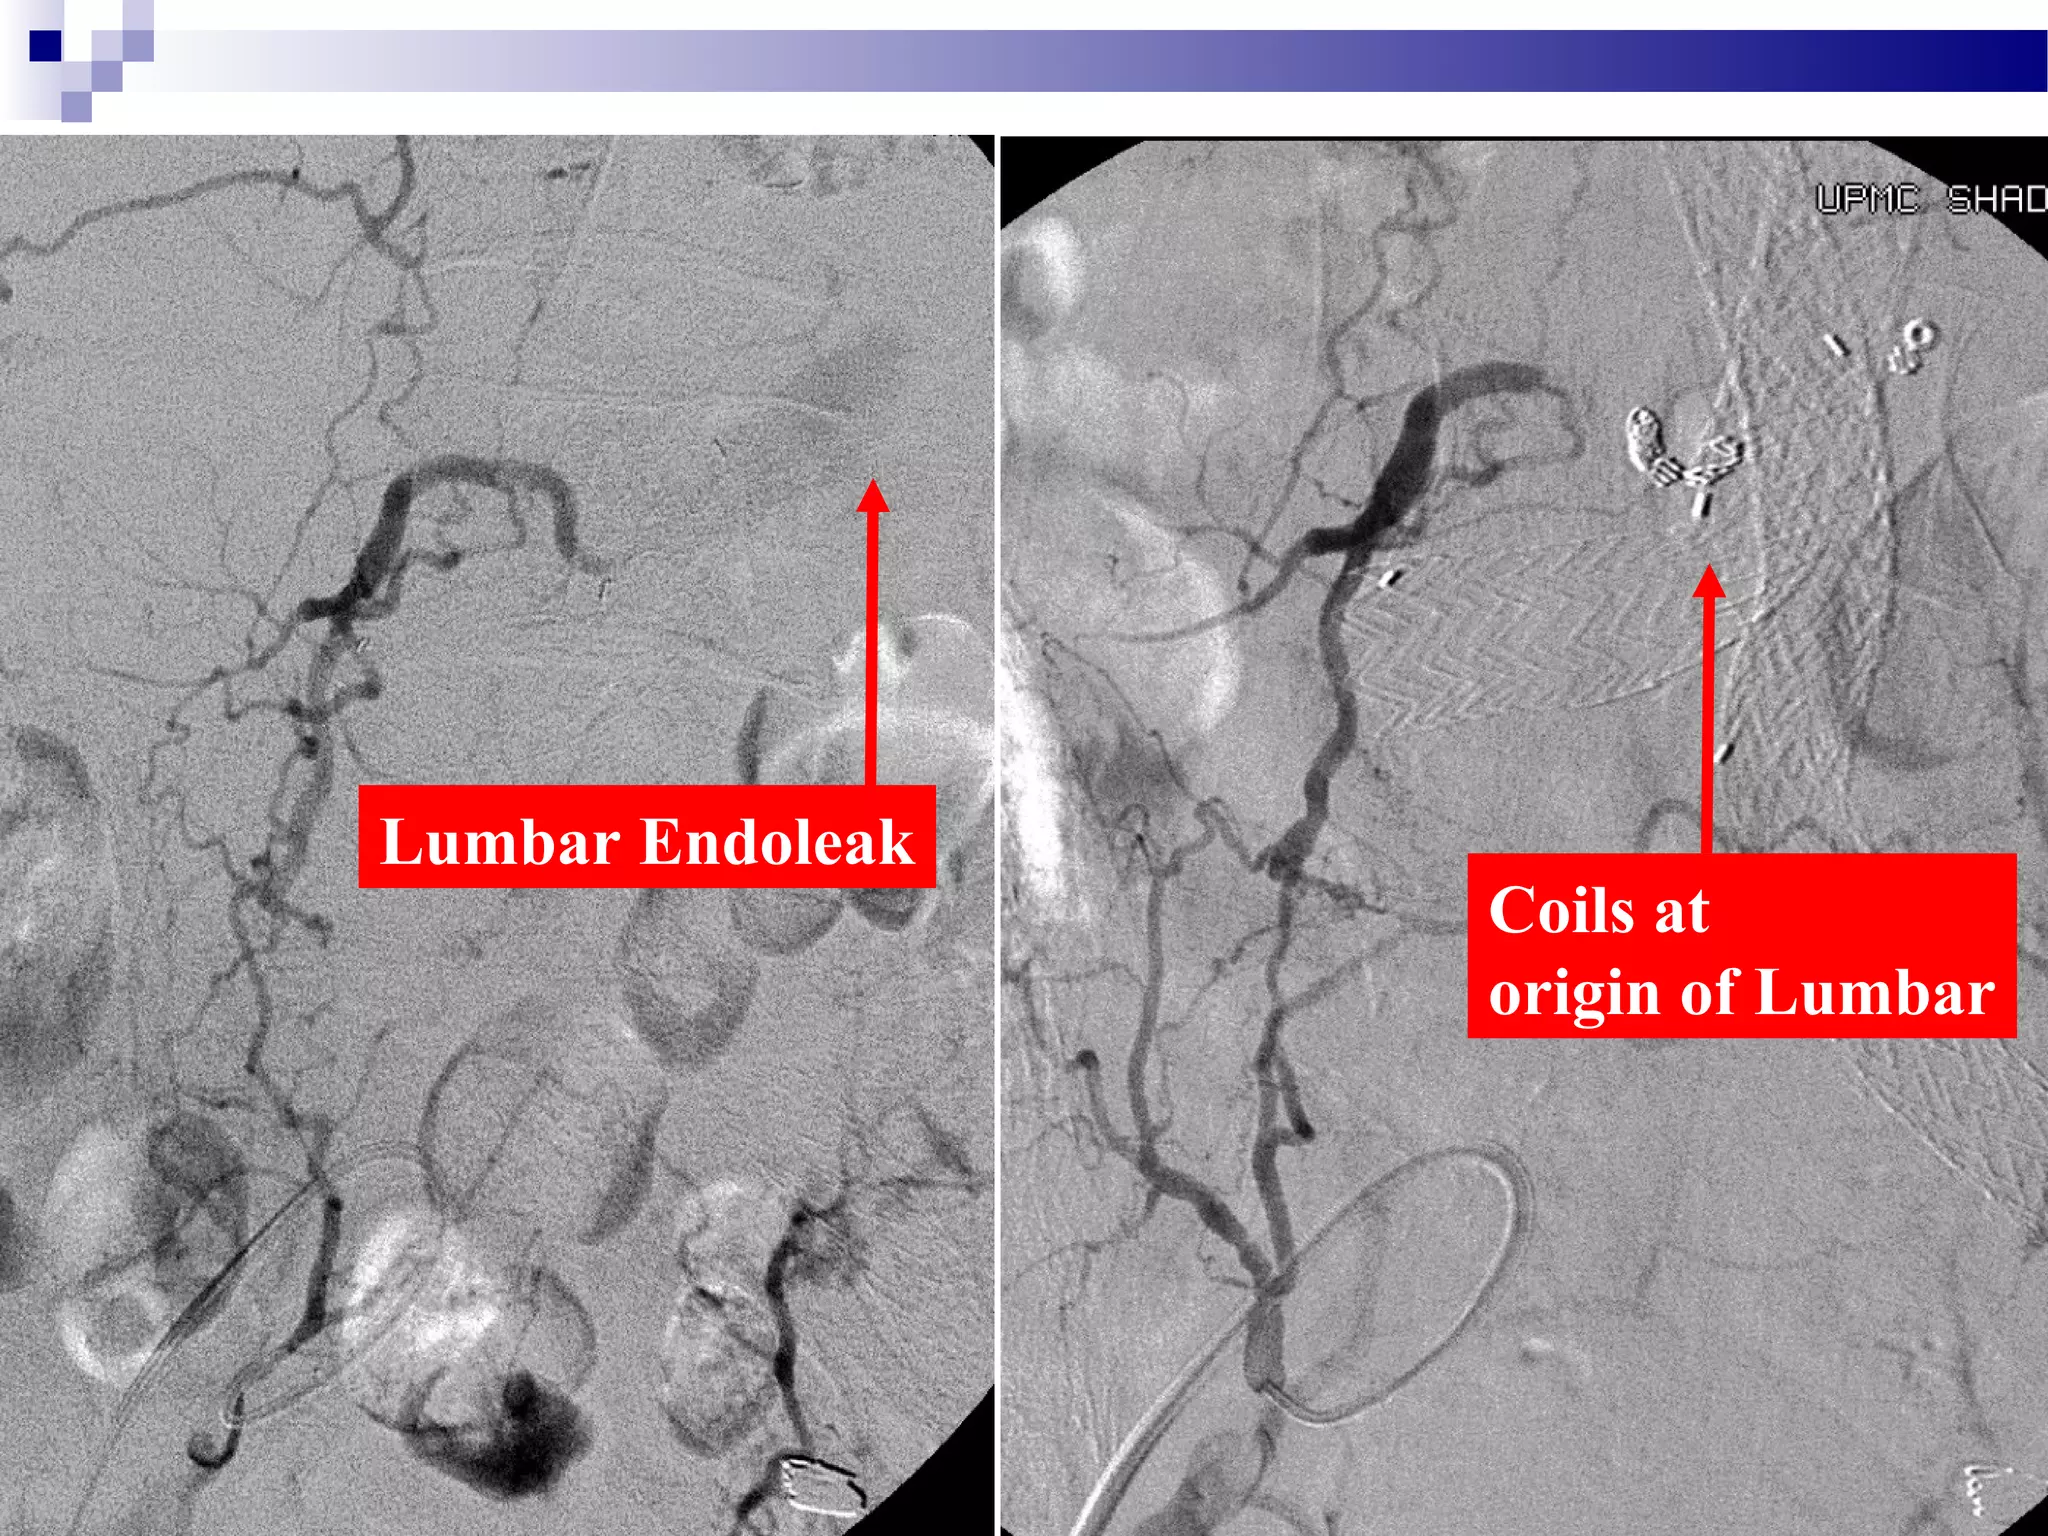

Lumbar Endoleak

Coils at

origin of Lumbar

Lumbar Endoleak Coils in Lumbar

One month later